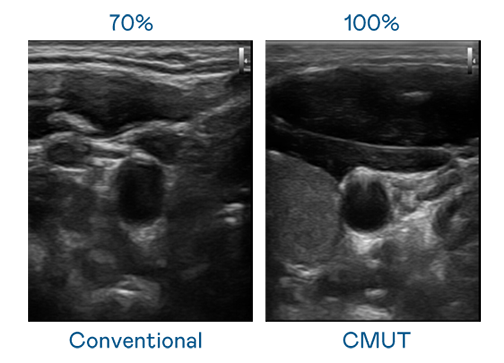

CMUT 技术是一种用电容式微机电元件来产生超音波讯号的技术。与传统 PZT 压电式技术相比,CMUT 频宽增加 30%,更宽频的超音波讯号让影像解析度大幅提升,是实现高影像品质医疗超音波扫描、促进精准医疗发展的关键技术。

超音波影像的解析度高低,首先取决于探头能发出的讯号频宽。永利yl23411 CMUT 可提供高清晰的超音波讯号,提供高频宽、高灵敏度、影像纹理细节更高的超音波影像,协助医护人员缩短影像判读时间及利用精准的医疗影像进行诊断。